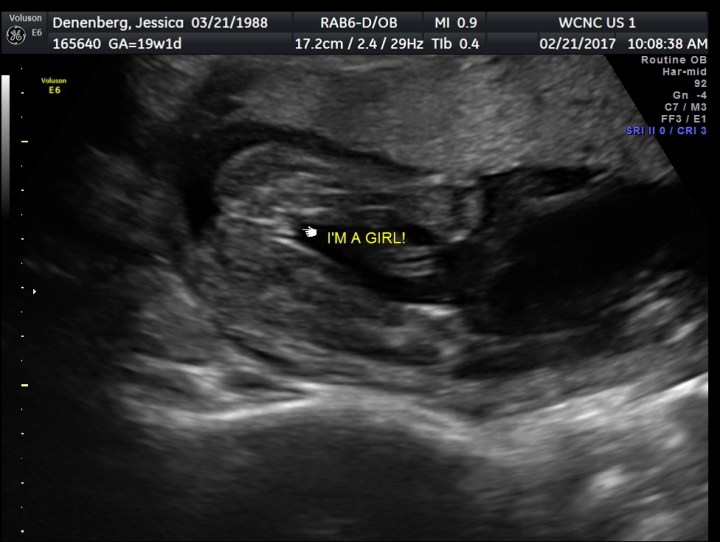

This past Tuesday, we had our first ultrasound. I didn’t really know how nervous I was for this until it was happening. There were so many “what ifs” and fears I carried with me until now. I have often read and heard and had friends experience heartbreaking losses when they get their 20 week ultrasound. We pray for those friends often.

We also praise God that we are having a healthy, fully developed, sweet baby GIRL!!!